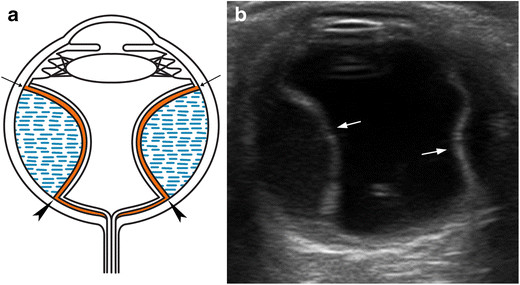

수술로 인해서 갑작스럽게 안압이 떨어지면 간혹 맥락막 박리가 발생할수 있습니다.

이는 수술전 안구내의 압력이 높다가, 수술로 인해서 압력이 순간적으로 줄어드니,

눈속의 구조물인 맥락막이, 껍질인 공막에서부터 허탈되어 떨어지는 것을 의미합니다.

이 경우, 안저검나사 B-scan 상에서 Choroidal detachment (맥락막 박리, CD)소견이 관찰됩니다.